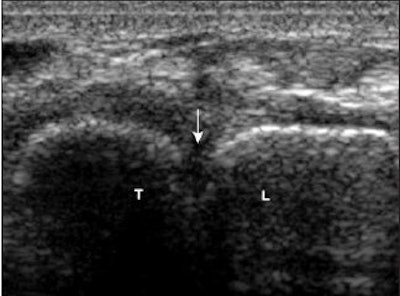

| Torn LTL. Above, transverse sonogram shows the dorsal aspects of the triquetrum (T) and lunate (L). The LTL fibers are not seen (arrow), which is consistent with a tear. Below, the LTL is not visualized on sonoarthrography (arrow) in the same patient. Note hypoechoic fluid extending between the triquetrum and lunate through the LTL tear. Intra-articular contrast improved visualization of the LTL tear. |